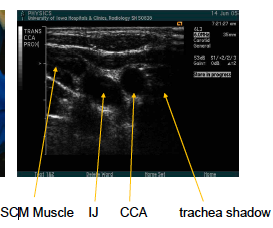

what are the arrows pointed to? what approach is being used?

trans CCA prox